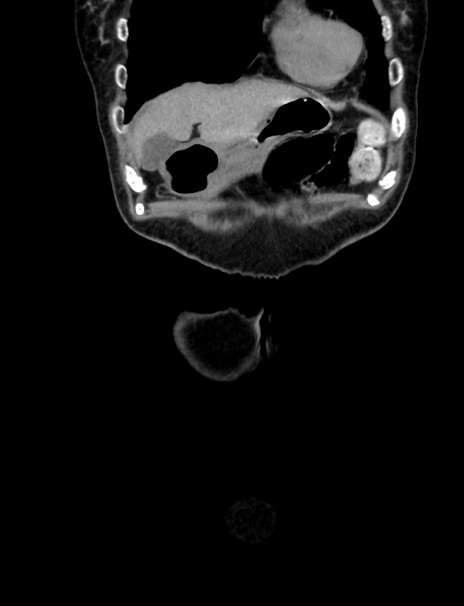

症例33(冠状断像)

【症例】70歳代 女性

【主訴】心窩部痛

【現病歴】延髄病変の精査・加療にて神経内科入院中。本日より心窩部痛あり。

【身体所見】右下腹部を中心に圧痛と反跳痛あり。

【データ】WBC 10900、CRP 0.02